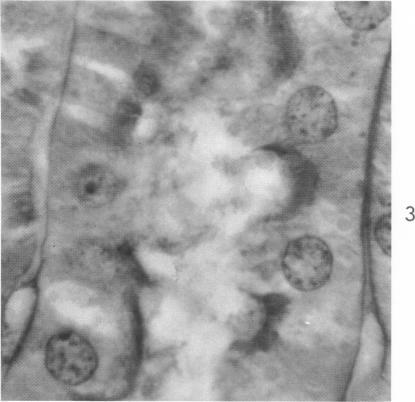

Intraluminal Nuclei and Other Inclusions as Agonal Artifacts of the Renal Proximal Tubules.

Am J Pathol. 1963 Jun;42(6):643-55.

Intraluminal Nuclei and Other Inclusions as Agonal Artifacts of the Renal Proximal Tubules.管腔内细胞核及其他包涵体作为肾近端小管濒死假象